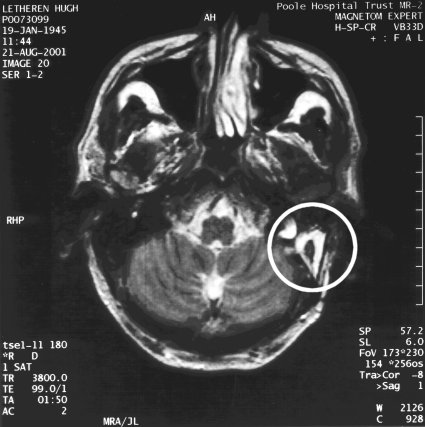

MRI Scan 2001

I had another MRI scan about 28 months after the operation to check on an unrelated problem, which proved to be clear. However, it clearly shows the area of my head which was excavated and filled with fat from my abdomen. This scan is similar to the one above but taken at a greater tilt to the horizontal, so it is difficult to make direct comparisons.